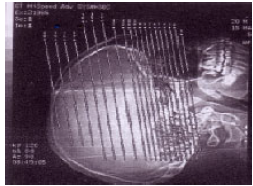

No planejamento tomográfico abaixo, pode-se afirmar que os cortes serão obtidos no plano

A

axial.

B

sagital.

C

coronal.

D

parassagital.